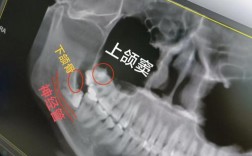

正畸治疗中,上颌智齿近中漂移是指第三磨牙在萌出或萌出过程中,因各种因素导致牙冠向近中(面部中线方向)倾斜或整体移动的现象,这一现象在正畸临床中较为常见,尤其好发于青少年及年轻患者群体,其发生机制复杂,可能对正畸疗效及口腔健康产生多方面影响,...